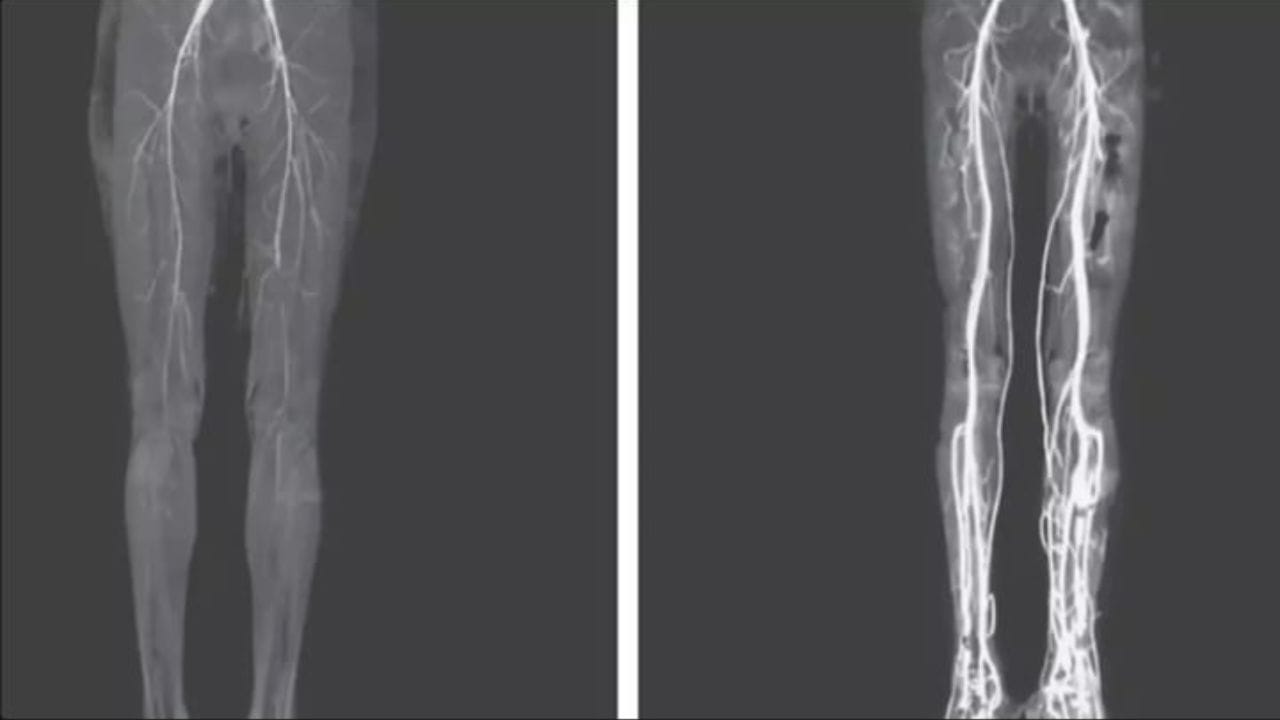

যুবতীকে দেখেই চমকে যান চিকিৎসকেরাও। পরীক্ষা করে দেখেন তাঁর পায়ের রং ফ্যাকাসে হয়ে গিয়েছে। হাঁটতেও অসুবিধা হচ্ছিল যুবতীর। আরও খতিয়ে দেখতেই চিকিৎসকরা বুঝতে পারেন, মহিলার দুটি পা প্রায় বরফের মতো ঠান্ডা। অথচ তীব্র জ্বালা কমছে না কিছুতেই। এমনকি পপলাইটাল এবং ডোরসালিস পেডিস ধমনীতে কোনও সার খুঁজে পাননি চিকিৎসকেরা।

এরপরেই সিটি স্ক্যান করে দেখা যায় যুবতীর পায়ের ধমনী সরু হয়ে গেছে। ফলে রক্ত সঞ্চালনে ব্যঘাত ঘটছে। সেই কারেণ এই সমস্যা। প্রাথমিক ভাবে চিকিৎসকরা ওই যুবতীকে রক্ত পাতলা করার একটি ওষুধ দেন। যা খেয়ে রক্তের প্রবাহ বাড়ে ফলে পায়ের তাপমাত্রা ফিরে পায়।